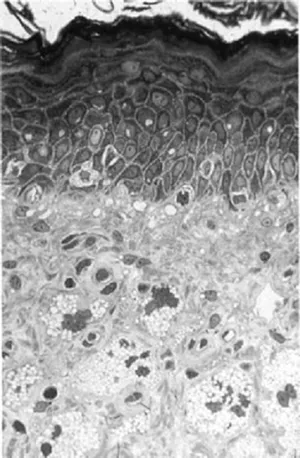

Under the microscope the epidermis is an obvious superimposition of cell layers, each clearly different from the others, these being the maturing phases of the keratinocytes (Fig. 1.3).

Figure 1.3 Image of a skin section seen under the light microscope, from the dermis to the upper epidermis (semi-thin section). The different layers of the epidermis are well visible. In the dermis istyocites and between the dermal fibres are other dermal cells.